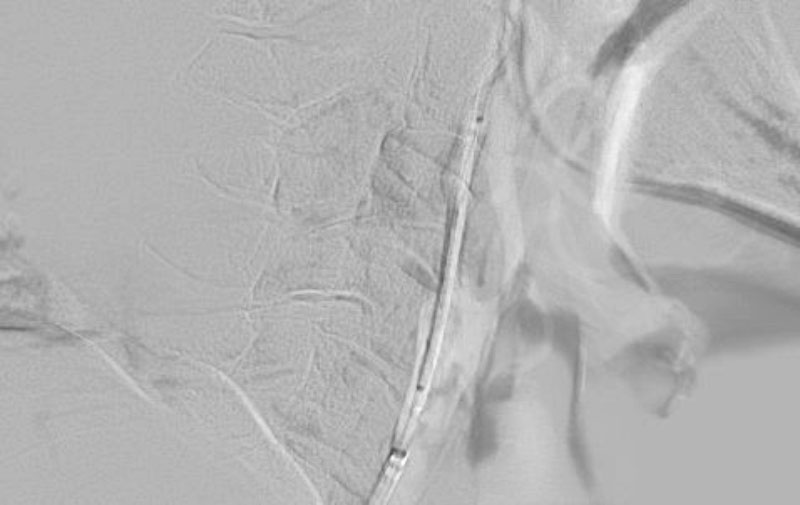

1346

'23年2月20日

右頚部内頚動脈狭窄症

80代

大阪府の病院

手術写真

中

治療

'23年2月